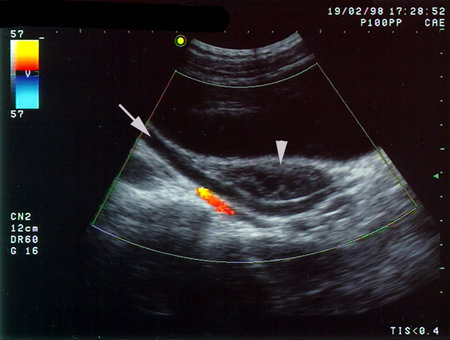

Мочевой пузырь "подготовлен" для исследования органов малого таза.

Типичная ситуация при этом - атония верхних мочевых путей ("необструктивный легкий уретерогидронефроз"). Изменения исчезают через некоторое время после микции.

Стрелкой обозначен мочеточник, наконечник стрелы со стороны мочевого пузыря указывает на неизмененный яичник.